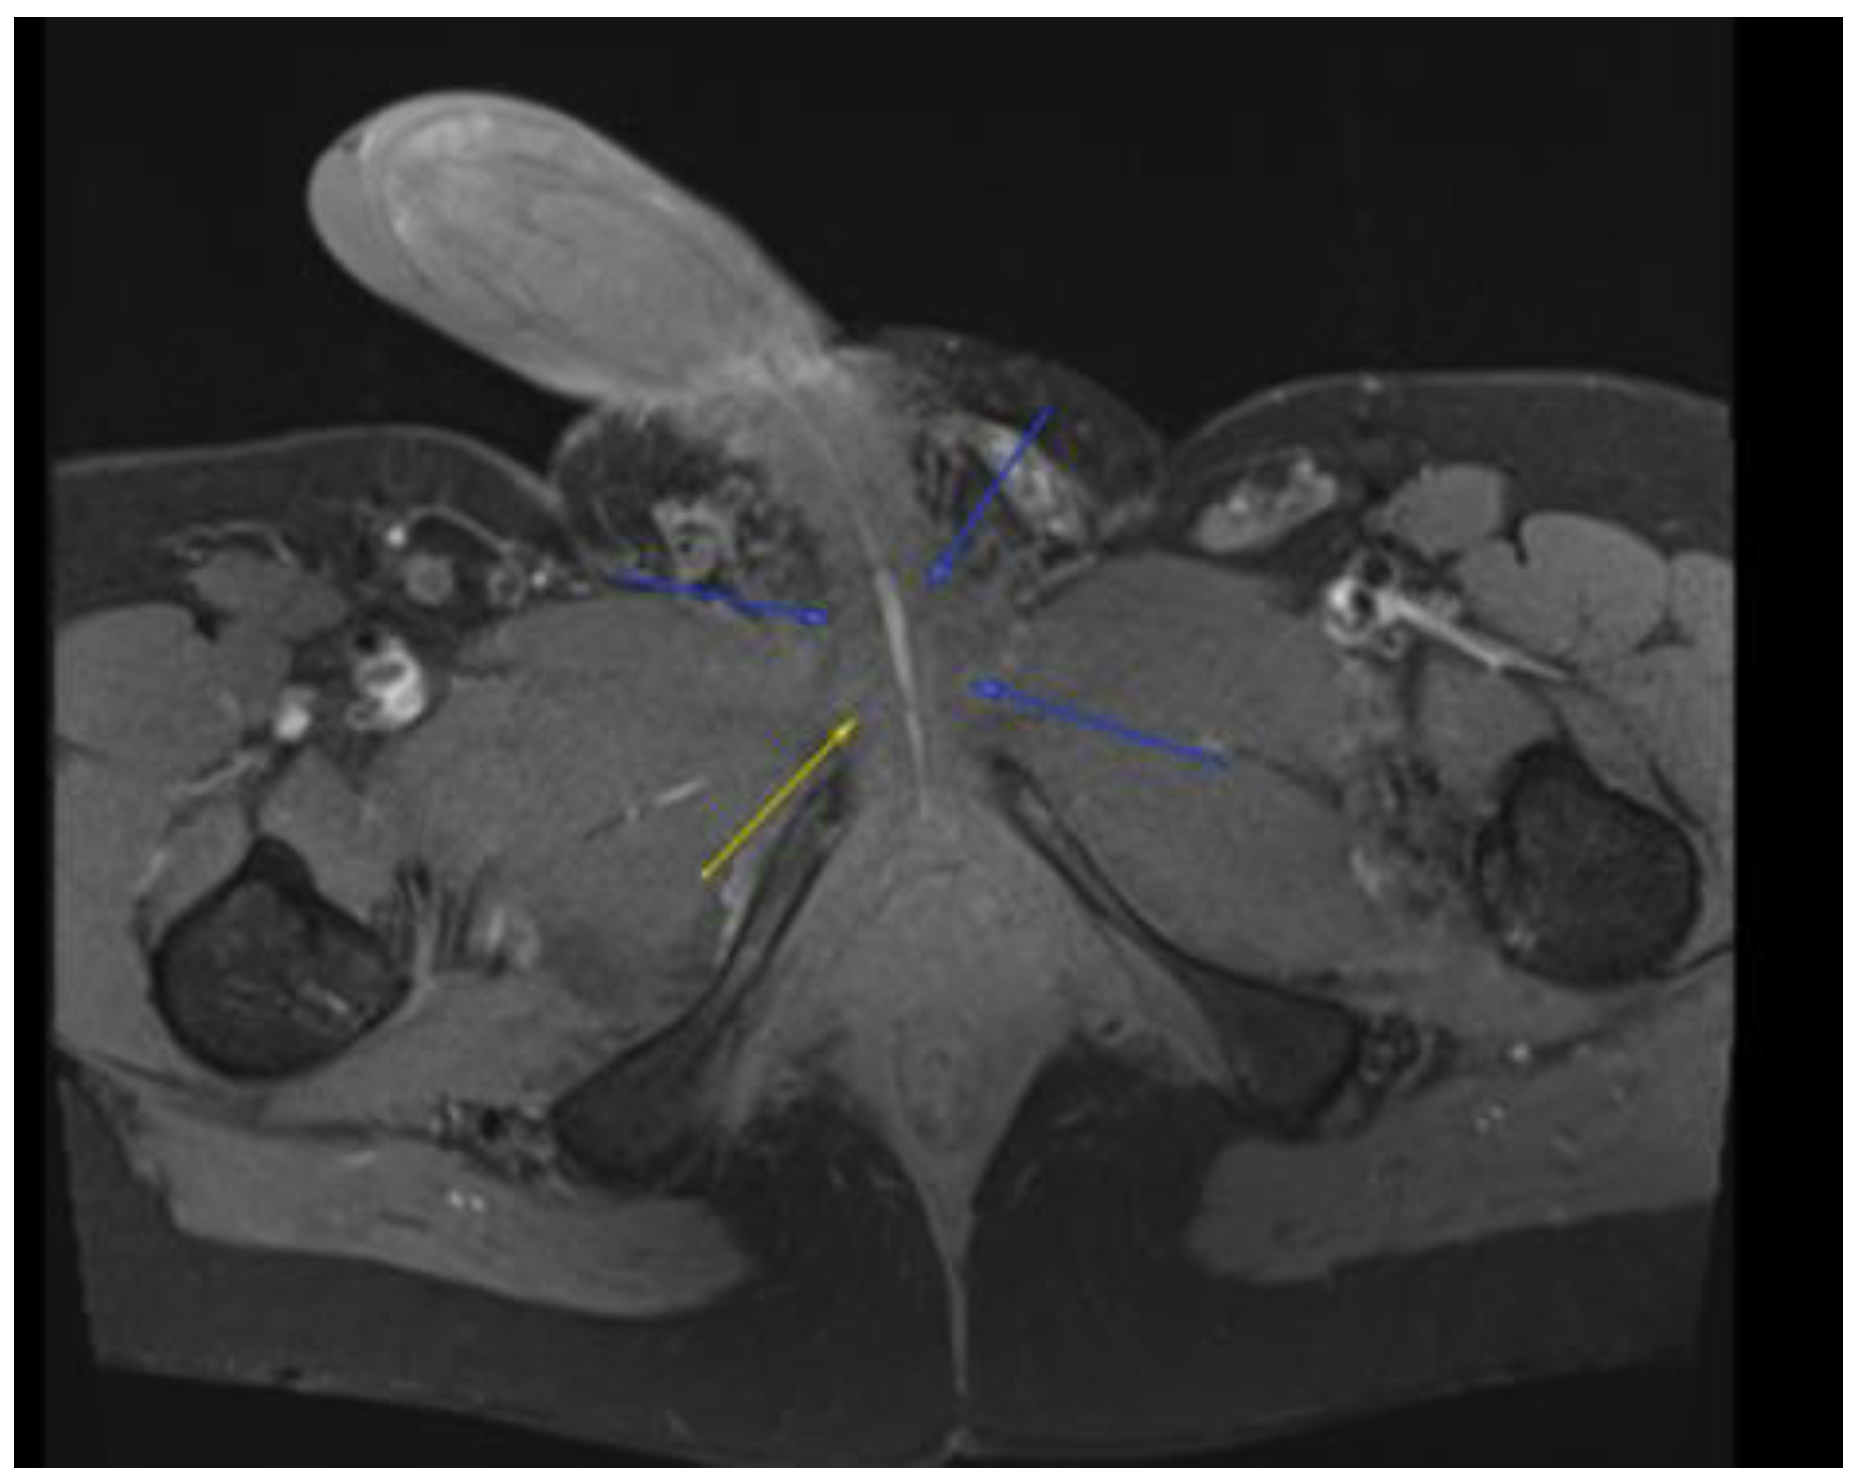

Figure 3.

MRI in the axial view T1 TSE FS PRE showing hyperintense linear non-enhancing structure consistent with ultrasound finding of thrombosed dorsal penile veins.